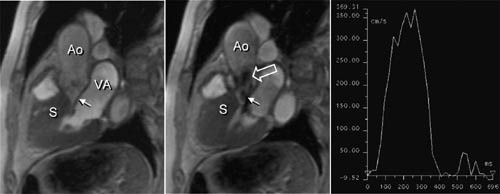

Høyre ventrikkel-dysplasi er bl.a. karakterisert av at myocyttene i høyre ventrikkels frie vegg helt eller delvis er erstattet av fett og bindevev (17). MR er den mest sensitive metoden til å påvise fettinfiltrasjon og redusert tykkelse av høyre ventrikkels frie vegg og kan derfor gi et viktig bidrag til diagnosen (fig 4). Slike funn er imidlertid ikke obligatoriske for diagnosen, og en normal MR-undersøkelse utelukker derfor ikke høyre ventrikkel-dysplasi. På den annen side vil MR kunne påvise karakteristiske forandringer også hos asymptomatiske personer med sykdommen, f.eks. slektninger til pasienter med verifisert høyre ventrikkel-dysplasi.